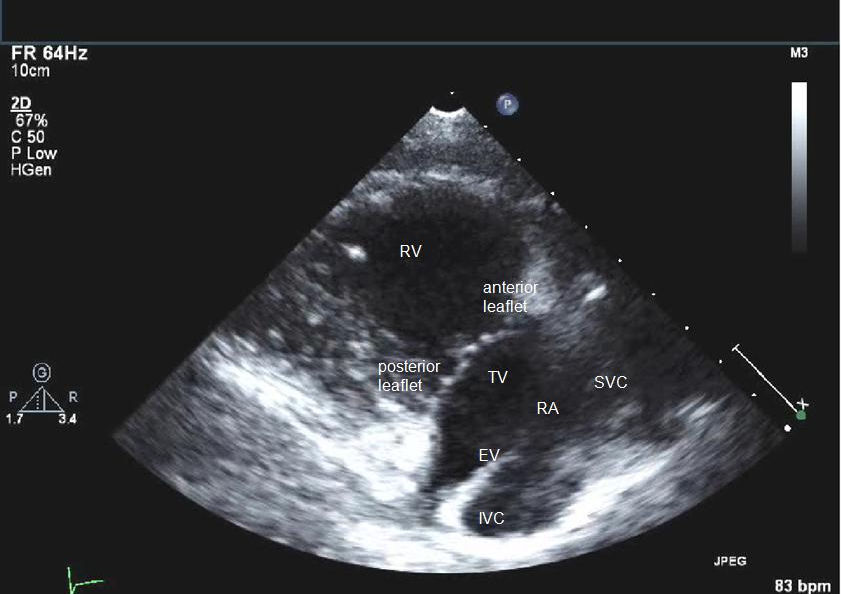

A

PLAX inflow view to visualise RV, RA, tricuspid valve

Q

what view are you trying to obtain?

PLAX inflow view

probe position to obtain PLAX inflow view?

cardiac probe at 4th ICS, notch pointed towards right shoulder

tilted medially towards patient

what structures are you trying to visualise on PLAX inflow view?

helps evaluate tricuspid valve function (look for TR)

ideally won’t see LV at all